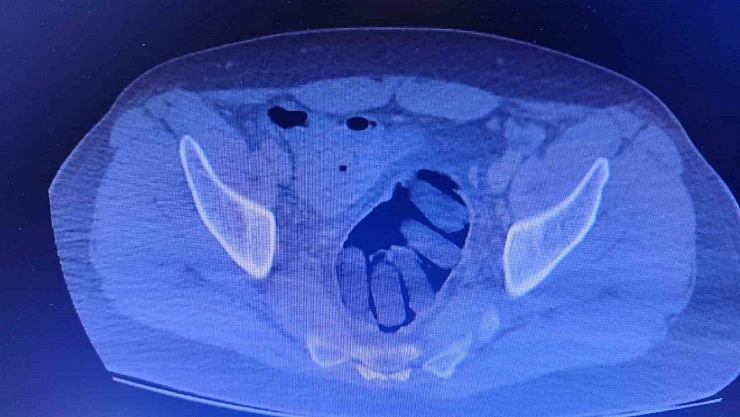

Kırşehir İl Emniyet Müdürlüğü Narkotik Suçlarla Mücadele Şube Müdürlüğü ekipleri tarafından yapılan çalışmalarda yabancı uyruklu Y.S. ve H.S.’nin doğu illerinden ülkeye kaçak yollarla girdikleri ve batı illerine uyuşturucu madde kuryeliği yaptıkları tespit edildi. Takibe alınan uyuşturucu kuryelerinin seyahat ettiği yolcu otobüsü Kırşehir’de durduruldu. Gözaltına alınan ve hastaneye götürülen şahısların midelerinde kapsül bulunduğu tespit edildi. Şahısların midelerinde zulaladığı 126 kapsül halinde 1 kilo 300 gram ve 44 kapsül halinde 550 gram uyuşturucu madde ele geçirildi.